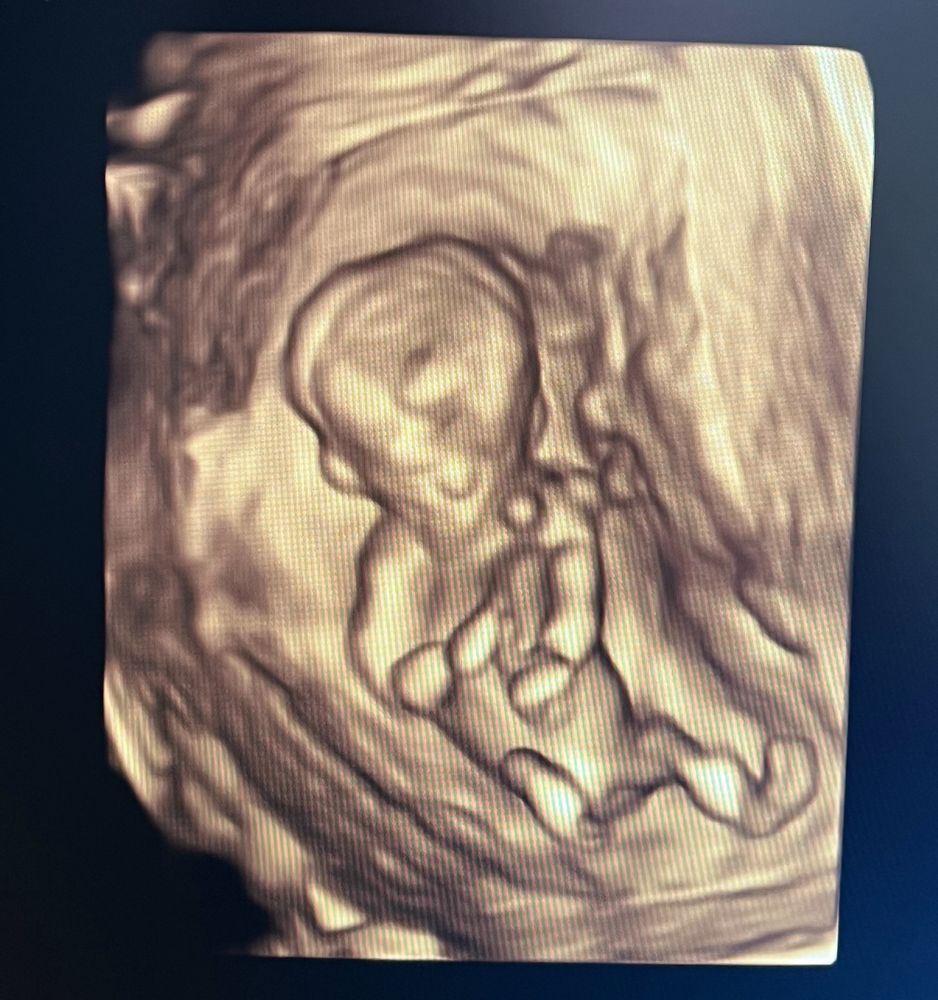

Скрининг 1

Кто в животике живёт (гадаем по фото УЗИ; результаты НИПТ или УЗИ)

Врач сказала, что может предположить пол, но говорить не будет, это ее принцип. А мне конечно интересно) кто разбирается, видно мальчик или девочка?

12 недель 5 дней

По половому бугорку могу предположить пацана. У девочек он другой